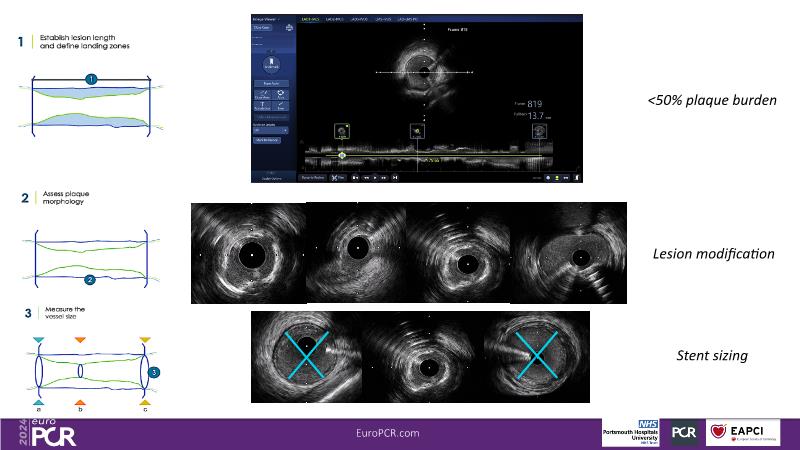

In this session, observe the enhanced user-friendliness of IVUS-guided complex PCI with improved AI algorithms, recognize the importance of combining experience with advanced knowledge of tools and techniques for optimal PCI outcomes in heavily calcified stenoses, and understand how tailoring drug-eluting devices for calcified lesions can streamline procedures without compromising clinical efficacy.

- To learn about the new AI-assisted IVUS image interpretation

- To share experience on an algorithmic approach, through an IVUS 123 workflow, in performing modern PCI in heavily calcified stenoses

- To tailor treatment through the choice of the most suitable drug eluting device according to the given anatomic setting